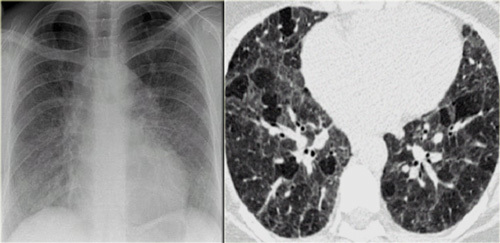

63M with chronic cough

Lung Adenocarcinoma

mixed ground-glass and solid consolidation –> “cancers that look like PNA”

-> lymphoma also looks like PNA

43yo F with SLE presents with dyspnea

Pericardial Effusion

cardiac shadow is enlarged but the pulmonary vessels are not dilated –> suspect a pericardial effusion.

azygous vein and SVC may be dilated, reflecting the elevated central venous pressure necessary to maintain right ventricular filling.

mediastinal interface over the left hilum in the absence of enlargement of the pulmonary arteries should also alert you to possibility of a pericardial effusion (fluid accumulating in a pericardial recess) because an enlarged cardiac chamber, such as the left atrial appendage, will not produce an interface this high along the left cardiac border.